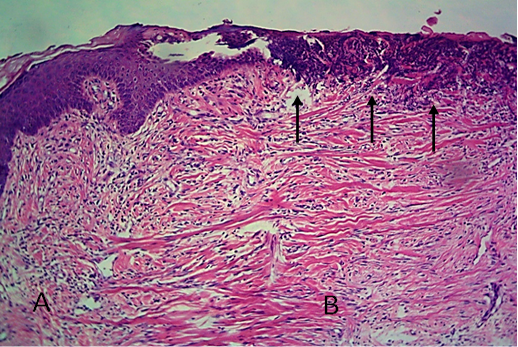

Histological section of autograft site of dog’s leg after one month of surgery. Showed original tissue (A) and grafted tissue (B). Extension of collagen fiber to connect the wound sides (arrowhead). H&E, 100x.

Histological section of autograft site of dog’s leg after one month of surgery. Showed grafted tissue (A) with the restoration of the epidermis layer (arrowhead) and formation of spongiosum layer (arrow).